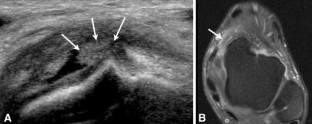

Fig. 3